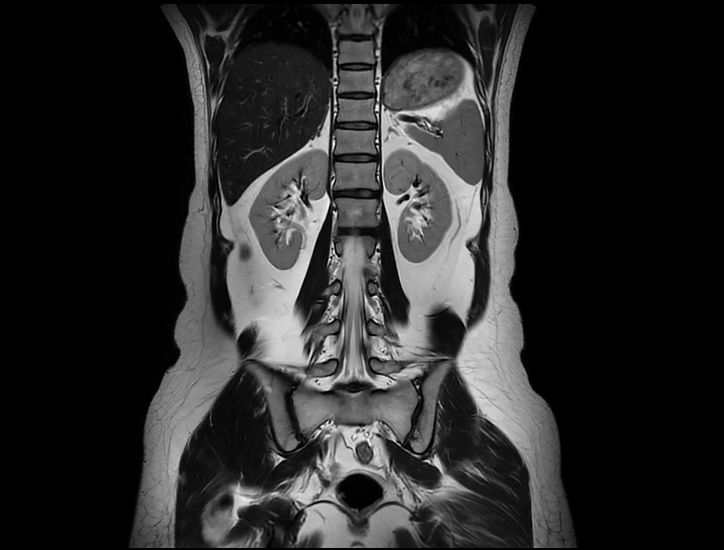

60 cm 超大视野腹部 T2W

全身弥散 DWI